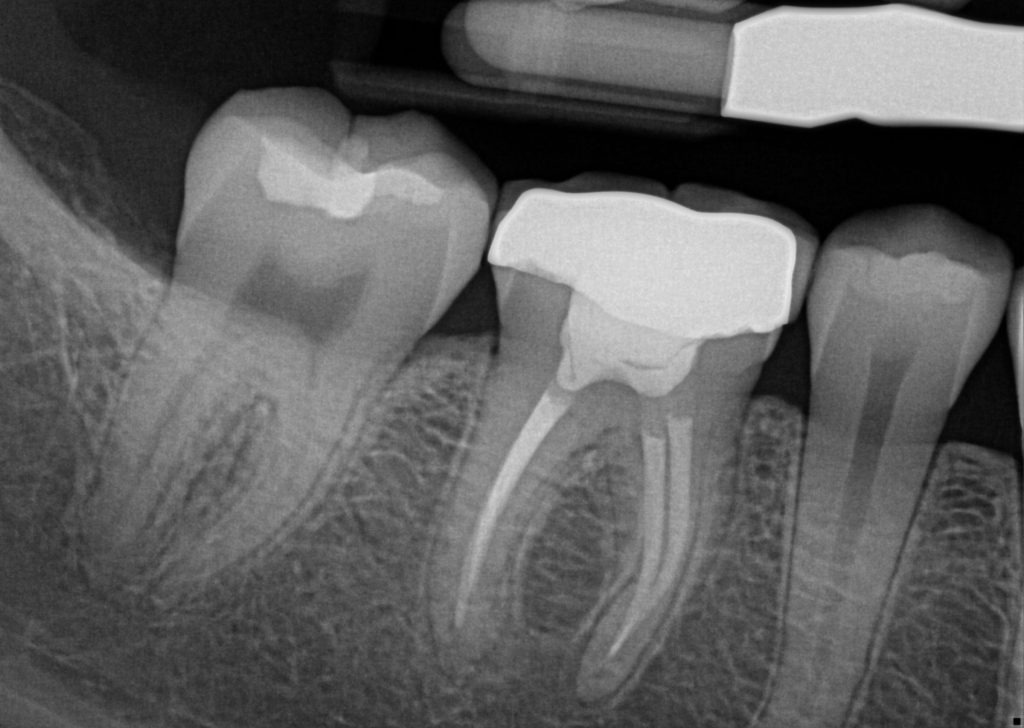

Root Canal Treatment RCT is a dental procedure used to treat infection or damage inside a tooth. It involves removing the infected pulp, cleaning and disinfecting the root canals, and sealing them to prevent future infection. RCT helps relieve pain, stop the spread of infection, and preserve the natural tooth instead of extracting it. With modern techniques and anesthesia, the procedure is safe, effective, and usually comfortable for patients. Dr. Ankita’s specialty lies in providing patient-focused dental care with an emphasis on precision, comfort, and long-term oral health. She is known for her careful approach to root canal treatments, using updated techniques and technology to ensure minimal discomfort and predictable results. Her focus on patient education and gentle care helps patients feel confident and at ease throughout their treatment.